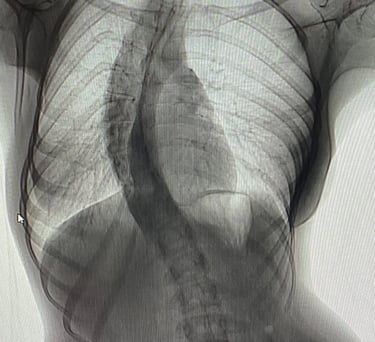

TEDAViLERiMiZ

Prof. Dr. Söyüncü çocukluk ve yetişkin döneminde karşılaşılan skolyoz, kifoz, bel ve boyun fıtıkları ve spinal kanal darlıkları, omurga enfeksiyonları, tümörleri, travmatik ve osteoporotik kırıkları gibi her türlü omurga rahatsızlıklarının tedavi ve cerrahileri ile diğer ortopedik rahatsızlıkların tedavileri ile ilgilenmektedir.